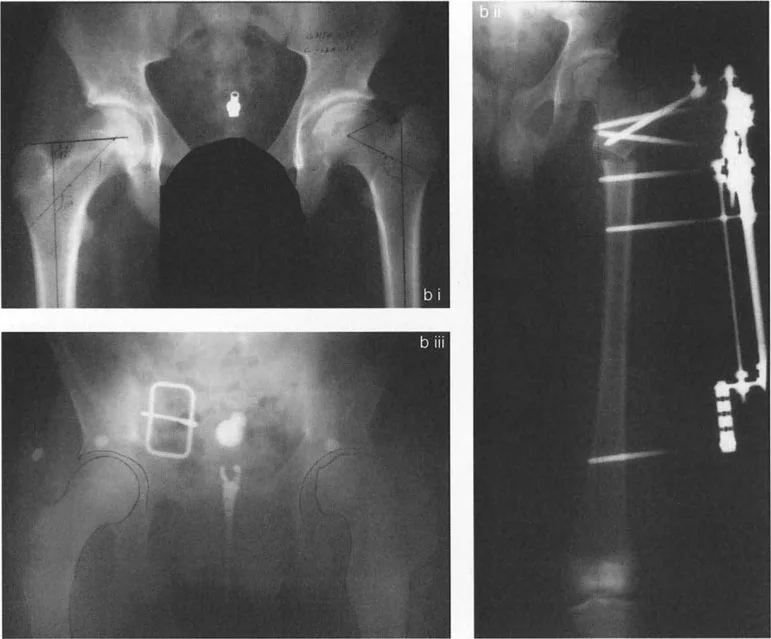

• الورك الفحجاء (Coxa Vara): تشوه يتميز بانخفاض زاوية عنق الفخذ (NSA) إلى أقل من 120 درجة، مما يجعل عنق الفخذ أكثر أفقية. يمكن أن تكون خلقية أو مكتسبة (مثل انزلاق المشاش الرأسي الفخذي SCFE).

• الورك الروحاء (Coxa Valga): تشوه يتميز بزيادة زاوية عنق الفخذ (NSA) إلى أكثر من 135 درجة، مما يجعل عنق الفخذ أكثر عمودية.

• انزلاق المشاش الرأسي الفخذي (Slipped Capital Femoral Epiphysis - SCFE): حالة تحدث عادة في المراهقين حيث ينزلق رأس الفخذ عن عنقه عبر لوحة النمو، مما يؤدي إلى تشوه.

* الأشعة السينية (X-rays): هي الخطوة الأولى والأكثر شيوعًا. توفر صورًا مفصلة للعظام وتسمح بقياس الزوايا المهمة مثل زاوية عنق الفخذ (Neck-Shaft Angle - NSA) وزاوية محاذاة الفخذ القريبة (Proximal Femoral Alignment Angle - PFAA).

تقييم زوايا التشوه

يستخدم الدكتور هطيف قياسات دقيقة من الأشعة السينية لتحديد مدى التشوه:

* زاوية عنق الفخذ (NSA): الزاوية بين عنق الفخذ وجسم عظم الفخذ. تُشير قيمها المنخفضة إلى الورك الفحجاء، والعالية إلى الورك الروحاء.

* زاوية محاذاة الفخذ القريبة (LPFA): زاوية مهمة لتقييم محاذاة عظم الفخذ.

* مركز دوران الزاوية (Center of Rotation of Angulation - CORA): نقطة افتراضية يتم تحديدها لتخطيط قطع العظم بدقة لضمان أفضل تصحيح للمحاذاة.